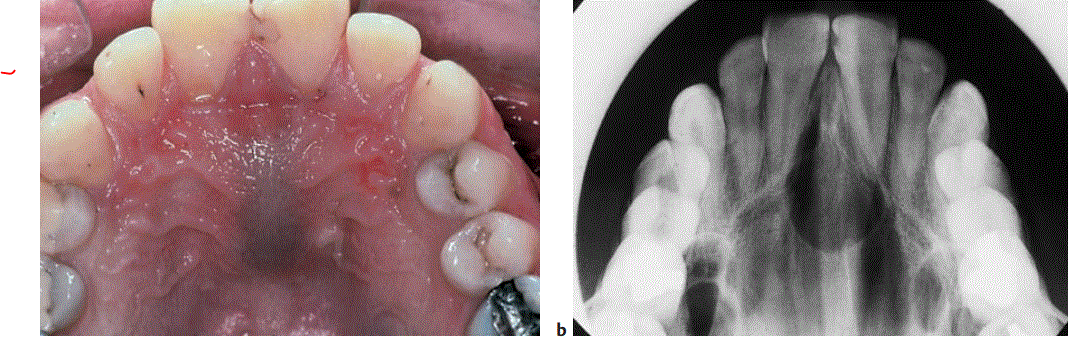

Ductus Nasopalatinus- IncisivisKanalZyste ,

gehört der Gruppe dysgenetische nicht odontogene/Fissurale Zysten.

Differentialdiagnostisch könnte auch radikuläre Zyste in Frage kommen, röntgenologisch schwer einschätzbar da fälschlicherweise die Wurzel der Front in die Ductus nasopalatinus Zyste ragen können und die Diagnose radikuläre Zyste sich stellen kann.

Weiter DD’s zu D.Nasopala-´.Z.:

Beschreibe Röntgenbild